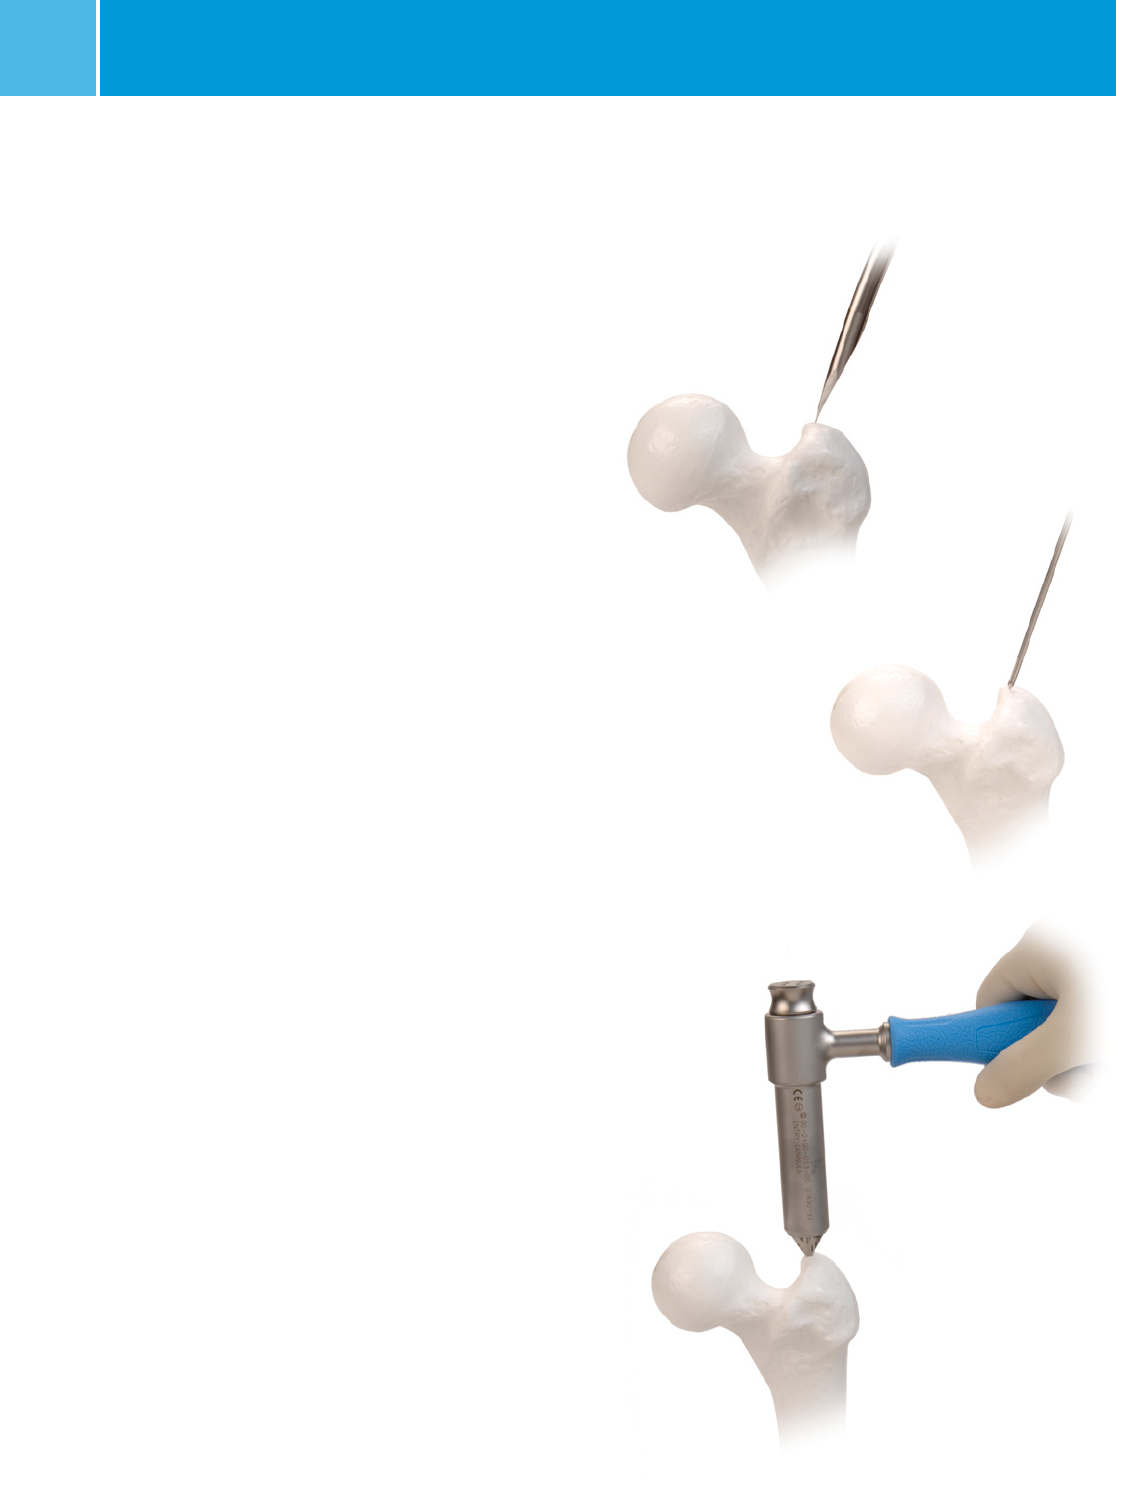

Greater Trochanter Entry Point

Starting Point Location

The starting point for the nail is located on the tip of the greater

trochanter (Figure 1). On the AP image, the starting point

should be on the tip of the greater trochanter, not lateral. On

the lateral image, the starting point should be in the midpoint

of the greater trochanter. For a proximal femur fracture where

recon screws will be used, the entry point on the lateral image is

at the junction of the anterior 1/3 and the posterior 2/3 of the

greater trochanter.

Begin the skin incision 3cm proximal to the greater trochanter.

A larger incision may be desired for obese patients. Split the

fascia of the gluteus maximus in line with its fibers. Identify

the subfascial plane of the gluteus medius, and palpate the

posterior tip of the greater trochanter. A 3.0mm threaded pin

can also be used to create a stab incision and advanced down

to the greater trochanter (Figure 2). The ENTRY CANNULA

STARTING POINT LOCATOR placed inside the ENTRY CANNULA

can also assist with dissection down to the bone (Figure 3).

Fig. 1

Fig. 2

Fig. 3

Piriformis Fossa Entry Point

The starting point for the nail is located in the piriformis fossa

for a standard shaft fracture (Figure 1). For a proximal femur

fracture where recon screws will be used, the entry point is 5mm

anterior to the normal piriformis entry point. Begin the skin

incision 3cm proximal to the greater trochanter. A larger incision

may be desired for obese patients. Split the fascia of the gluteus

maximus in line with its fibers. Identify the subfascial plane of

the gluteus medius, and palpate the posterior tip of the greater

trochanter. A 3.0mm threaded pin can also be used to create a

stab incision and gain entry into the fossa (figure 2). The ENTRY

CANNULA STARTING POINT LOCATOR placed inside the ENTRY

CANNULA can also assist with dissection down to the bone

(Figure3).